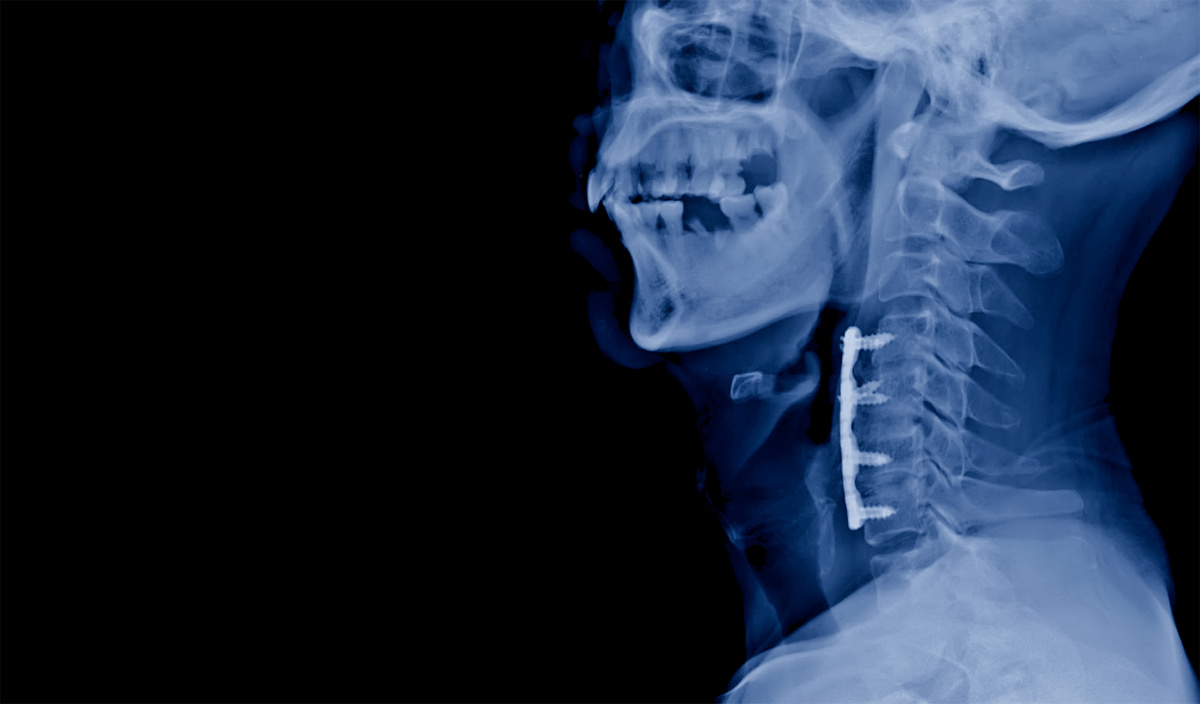

ACDF is a surgical procedure performed through a small incision at the front of the neck. The surgeon accesses the cervical spine from the anterior, or front, side and removes a damaged or degenerated disc that is compressing neural structures. Once the disc has been removed, a bone graft or interbody cage is placed in the empty disc space to restore height and stability, and a metal plate is typically secured to the adjacent vertebrae to hold everything in position while the bones fuse together over time.

Once the damaged disc is identified and removed, any bone spurs or disc fragments pressing on the nerves or spinal cord are carefully cleared away. The interbody graft is then placed, and the plate and screws are secured. Neuromonitoring is used throughout the procedure to track the function of the spinal cord and nerve roots in real time. The incision is closed in layers, and most patients spend one night in the hospital before being discharged the following day.